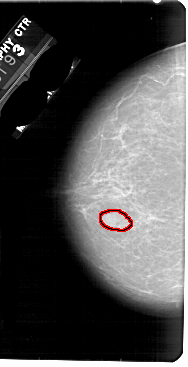

A_1793_1.LEFT_MLO

FILE: A_1793_1.LEFT_MLO.OVERLAY

TOTAL_ABNORMALITIES 1

ABNORMALITY 1

LESION_TYPE MASS SHAPE LOBULATED MARGINS OBSCURED

ASSESSMENT 4

SUBTLETY 4

PATHOLOGY BENIGN

TOTAL_OUTLINES 1

BOUNDARY